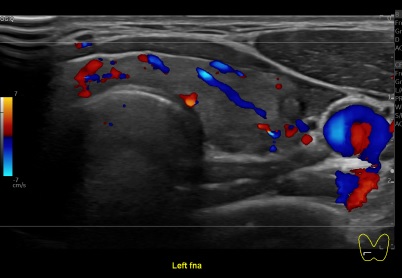

상기환자 외부검사이상 추적관찰위해 내원하신 40대초반 여성분으로

의심스러운 갑상선 좌엽 결절 세포검사 진행후 갑상선암으로 진단되었습니다